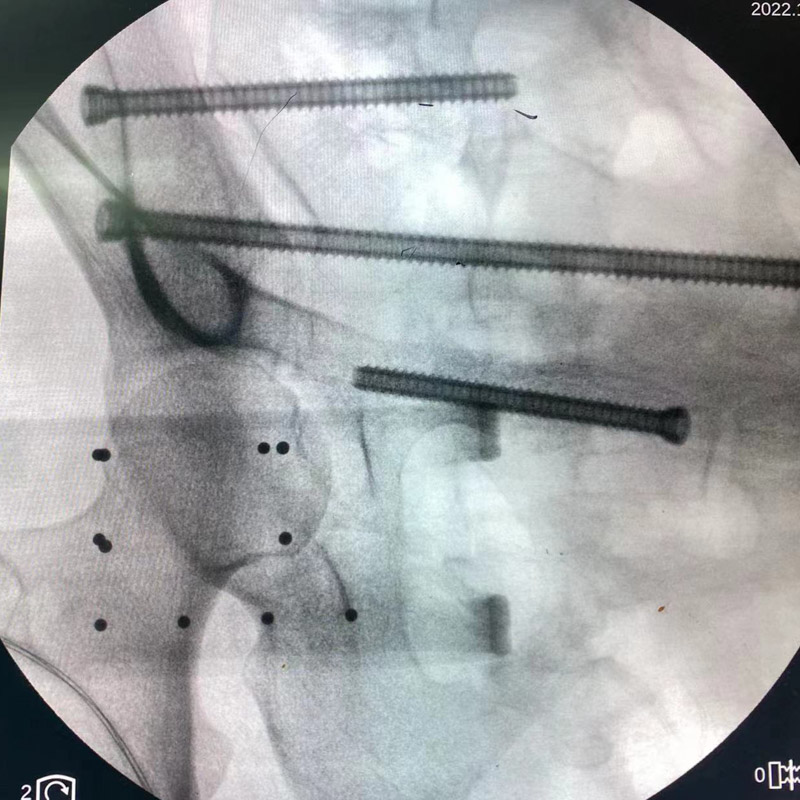

術(shù)中,創(chuàng)傷骨科團(tuán)隊(duì)將示蹤器安裝在患者手術(shù)處,與移動(dòng)C型臂X光機(jī)相配合,手術(shù)團(tuán)隊(duì)根據(jù)生成圖像模擬置釘,通過獨(dú)有算法計(jì)算出入釘點(diǎn)及釘?shù)溃凑招g(shù)中規(guī)劃,施術(shù)者借助導(dǎo)向套筒,為患者精準(zhǔn)的植入三枚螺釘,手術(shù)切口僅三個(gè)1厘米小洞,術(shù)中出血不到10毫升。